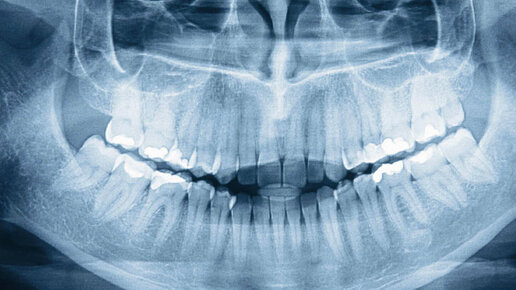

Ортопантомограмма (ОПТГ): когда нужен панорамный снимок зубов?

Благодаря развитию технологий, в стоматологии появились новые методы исследования зубного ряда и диагностирования заболеваний. Наиболее современным на сегодняшний момент является ортопантомограмма (ОПТГ) или, по-другому, панорамный рентгеновский снимок зубов. На полученном изображении отчетливо видны два ряда зубов, челюстное строение, верхнечелюстной сустав и носовые пазухи. Благодаря снимку, врач сможет диагностировать дефекты прикуса и верхнечелюстного сустава, состояние костной ткани и общую картину строения челюсти в целом...